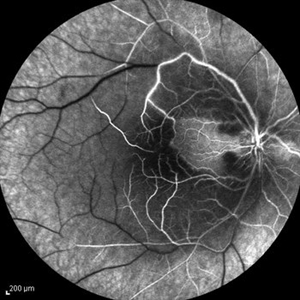

Behcet's Disease Behcet's DiseaseMar 13 2013 by Hamid Ahmadieh, MD Mid phase FA of the right eye of a 23-year-old man with retinal vasculitis and branch retinal vein occlusion (BRVO) due to Behcet's disease . Photographer: Solmaz Shahmohammad, Negah Eye Center, Tehran Imaging device: Heidelberg Spectralis Condition/keywords: branch retinal vein occlusion (BRVO), retinal vasculitis